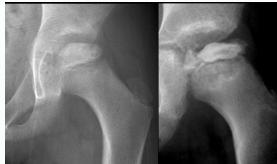

Imaging:

- Required views: AP and Frog lateral pelvis

- Key finding: Slippage of femoral epiphysis

Radiographic Examples:

Comparative views showing slipped vs. normal hip:

(Source: Apley’s System of Orthopedics and Fractures)

X-ray Diagnosis:

| View | Slipped Hip | Normal Hip |

|---|---|---|

| AP | ![]() | - |

| Frog Lateral | ![]() | - |